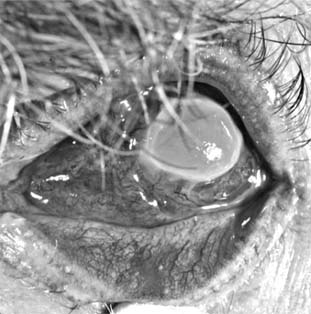

Pneumococcal corneal ulcer usually occurs 24-48 hours after inoculation of an abraded cornea. It typically produces a gray, fairly well circumscribed ulcer that tends to spread erratically from the original site of infection toward the center of the cornea (Figure 6-1). The advancing border shows active ulceration and infiltration as the trailing border begins to heal. (This creeping effect suggested the term "acute serpiginous ulcer.") The superficial corneal layers become involved first and then the deep parenchyma. The cornea surrounding the ulcer is often clear. Hypopyon is common. Scrapings from the leading edge of a pneumococcal corneal ulcer usually contain gram-positive lancet-shaped diplococci. Drugs recommended for use in treatment are listed in Tables 6-2 and 6-3. Concurrent dacryocystitis should also be treated.

Figure 6-1

Figure 6-1: Pneumococcal corneal ulcer with hypopyon.